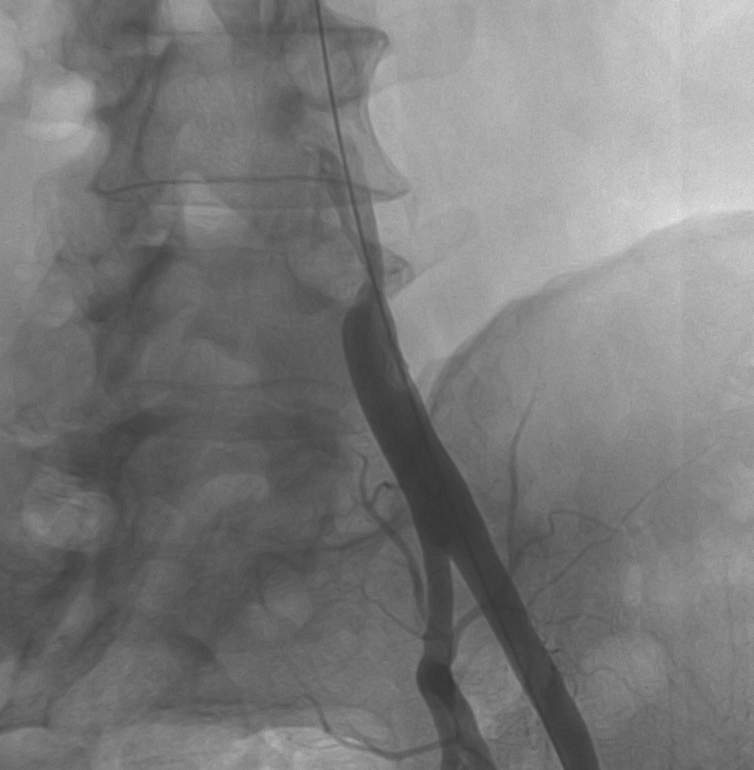

Seldinger technique is used for vascular access. Arterial puncture by a Seldinger needle (Fig 1, Upper row, left panel) is most often pulse-directed (by palpation), but can be accessed by ultrasound guidance. Most commonly used access sites are common femoral and brachial arteries, radial arteries are used mostly by cardiologists, popliteal artery can be rarely punctured in special cases (retrograde recanalisation of superficial femoral artery occlusion). A guidewire is inserted into the needle (Fig 1, Upper row, right panel), the needle is withdrawn (Lower row - left panel) (at this point the puncture site should be compressed to prevent bleeding); a few mm dissection may be done by a scalpel, the introducer sheath and then a catheter is fed onto the guidewire (Lower row - right panel); then the guidewire can be withdrawn and contrast medium can be inserted through the catheter. More information on contrast medium is available in chapter 7.

Figure 1.: Seldinger technique. Upper row – left panel: one-part Seldinger needle; Upper row – right panel: the femoral pulse was well palpable, the right common femoral artery was punctured using the Seldinger needle, then the guidewire was inserted into the needle. Lower row – left panel: the needle was withdrawn, manual compression was performed to prevent puncture site hematoma; Lower row - right panel: a 4F introducer sheath was inserted onto the guidewire. Contrast medium can be injected through the sheath.